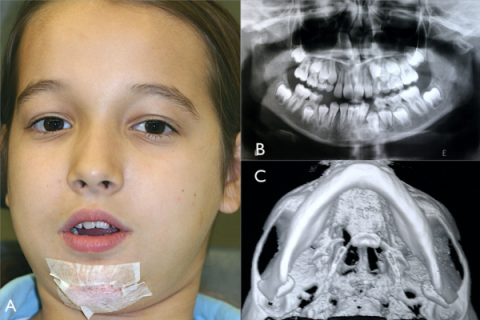

Pediatric Jaw Fracture Care

Gentle, specialized treatment for jaw fractures in children.

Distraction Osteogenesis

adual bone lengthening to correct facial deformities.

Jaw Cyst/Tumour Management

Safe removal and treatment of cysts or growths in the jaw.